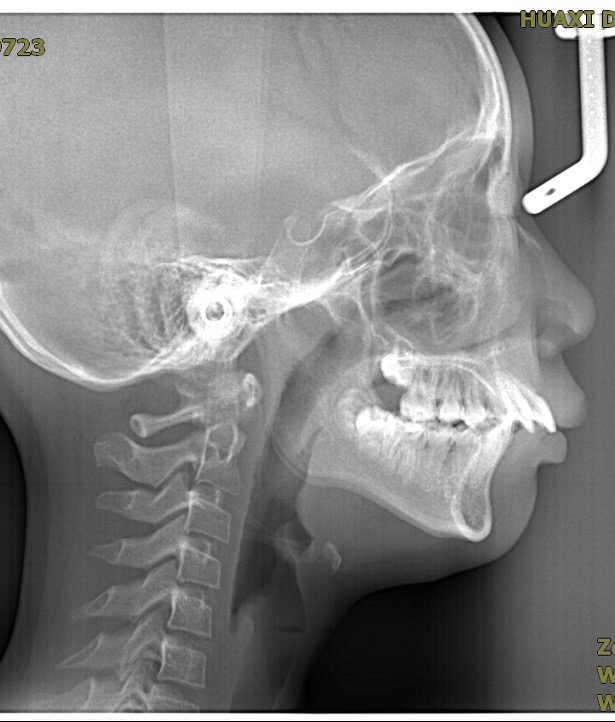

“一叶障目不见泰山”,同理,由于肌肉、脂肪的覆盖,我们很难看清骨骼的情况。因此,我们借助放射线来更好的观察骨骼的情况,有一项特别的放射线检查叫做头颅侧位片(图1)。

我们借助头颅侧位片进行头影测量分析(图2),可以分析上颌骨、下颌骨、牙齿、软组织的情况,这是所有专业正畸医生需要掌握的技能,有利于做出正确的矫正方案。同时,在结束矫正的时候对矫正前后进行头影测量分析(图3),可以分析矫正效果,知其然知其所以然。

当然,头颅侧位片的辐射剂量非常小,使用起来很安全,在矫正前、矫正中、矫正后均可以根据需要进行拍摄。